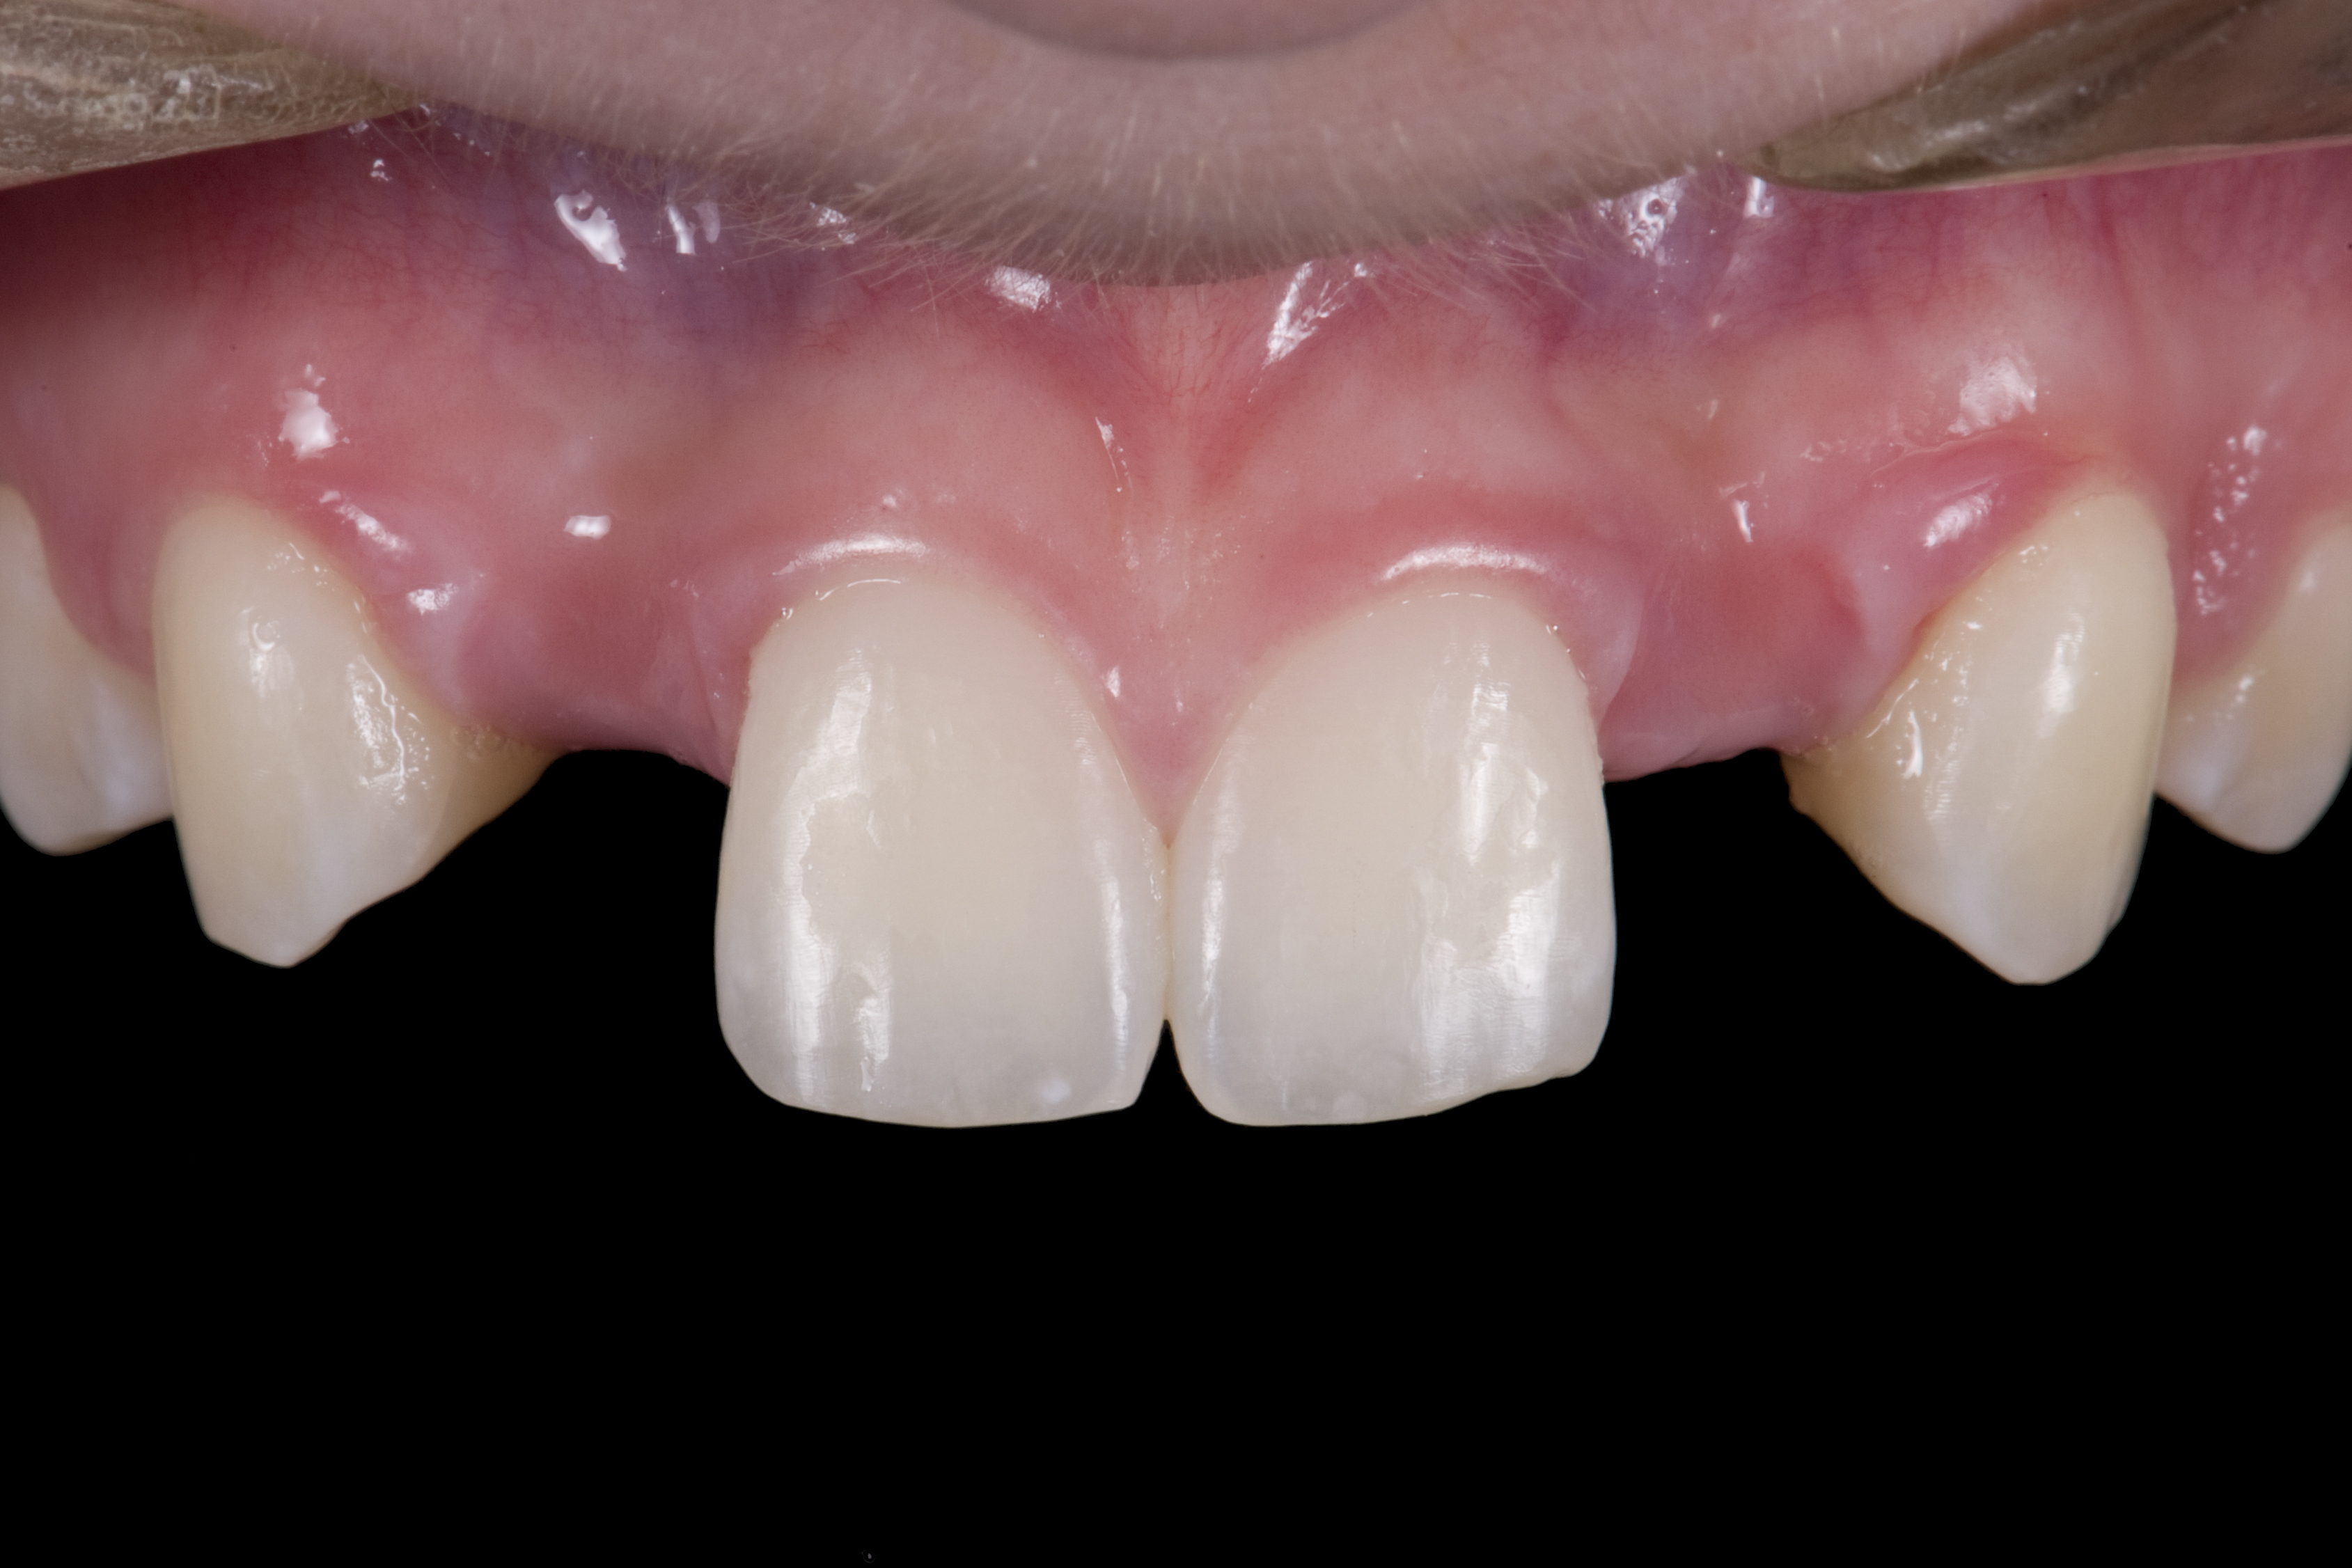

When the patient returned, the fit was evaluated in the mouth. Once verified, the internal surface of the framework was etched with a 9.5% hydrofluoric acid for 90 seconds and then salinized. After etching the enamel surface with phosphoric acid for 30 seconds and applying the primer (Single Bond Plus, 3M ESPE) to both the internal surface of the framework and the enamel, the zirconia bridge was bonded with a dual-cure resin cement (RelyX™ ARC, 3M ESPE). After the procedure, the patient ended up with a long-term, high-strength esthetic restoration advantaged by the bonding potential of fledspathic ceramic (Figure 20 through Figure 24). Six years after placement, the prosthesis had remained in place with no complications.

(20.) Facial view of final single-wing, modified zirconia resin-bonded bridges.

Figure 20

(21.) Smile view.

Figure 21